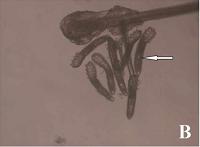

蠕形螨眼部感染的图片

蠕形螨感染

蠕形螨依靠吞噬睑板腺内脂质生存,不仅会破坏人类的眼部毛囊和睑板腺,它们代谢出的废物及死亡后的躯体还会引起毛囊和睑板腺的阻塞,形成睫毛根部圆柱状鳞屑,导致物理性的损伤。